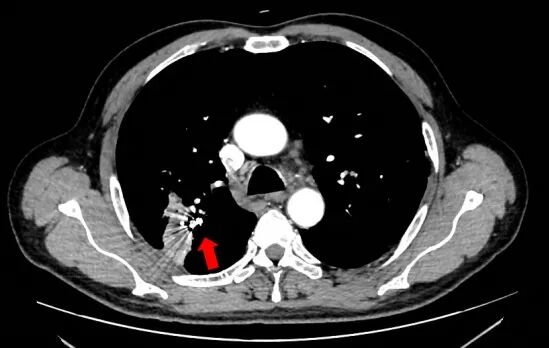

術(shù)前圖片:(紅色箭頭處為肺動(dòng)脈假性動(dòng)脈瘤)